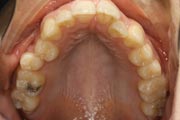

Crowding

After